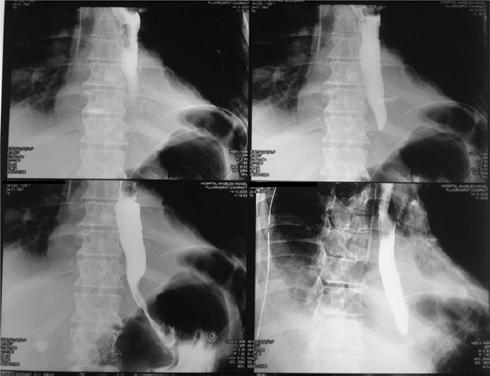

Por la localización de la perforación en el tercio inferior del esófago y la fuga del medio de contraste hacia el retroperitoneo se decidió someter al paciente, a las 4 horas de ingreso, a una laparoscopia para drenaje del líquido pleural, mediastinal y retroperitoneal observado en los estudios de imagen, así como a cierre primario con funduplicatura. El paciente ingresó a quirófano para laparoscopía, en la cual se localizó el hiato esofágico, donde se observó en su cara anterior una zona de mucosa irritada y se realizó disección del ligamento esofagofrénico, identificando los pilares y liberando los vasos cortos. Posteriormente se realizaron ventana retroesofágica y disección de hiato esofágico, donde se observó una perforación de la pleura derecha con presencia de abundante contenido gástrico en la pleura y el mediastino, y se identificó la zona de perforación en el tercio inferior de la cara lateral derecha del esófago, de 1.5 cm de longitud, que se cerró con sutura y pegamento. A continuación se realizó funduplicatura tipo Dor y se colocaron drenajes en hiato esofágico y subdiafragmático izquierdo, y sonda endopleural en el espacio pleural derecho. Al egreso del quirófano, el paciente ingresó a la unidad de terapia intensiva por choque séptico, con presión arterial de 80/50 mmHg, frecuencia cardiaca de 110 latidos por minuto, frecuencia respiratoria de 18 respiraciones por minuto, temperatura de 37.0 °C, saturación de oxígeno del 94%, fracción inspirada de oxígeno del 80% y llenado capilar de 5 s, requiriendo manejo vasopresor con norepinefrina a dosis de 0.19 μg/kg/min y vasopresina a dosis de 0.03 U/min, así como ventilación mecánica invasiva y nutrición parenteral (Fig. 5). Los resultados de los cultivos reportaron crecimiento de Candida glabrata sensible al voriconazol (≤ 0.12 μg/ml), por lo que se realizó escalamiento terapéutico y se logró la extubación a las 72 horas del ingreso a la unidad de terapia intensiva. Se realizó esofagograma de control a los 5 días del procedimiento quirúrgico y no se observó evidencia de fuga esofágica (Fig. 6). El paciente tuvo una evolución favorable, con resolución del cuadro de sepsis, reinicio y tolerancia de la vía oral, y egreso a los 10 días de ingreso hospitalario, con seguimiento posterior con estudio de imagen de control por consulta externa.

En la exploración física el paciente se encuentra despierto, escala de Glasgow 15 puntos, facies álgica, polipneico, con enfisema subcutáneo en la región supraclavicular y el tórax superior bilateral con crepitación, sin equimosis, con requerimiento de oxígeno suplementario por puntas nasales a 5 l/min, con disminución del murmullo vesicular en la región basal del hemitórax derecho y dolor abdominal a la palpación superficial y profunda en la región epigástrica, así como intolerancia al decúbito supino. El resto de la exploración no mostraba alteraciones, con los siguientes signos vitales: presión arterial 130/80 mmHg, frecuencia cardiaca 100 latidos por minuto, frecuencia respiratoria 20 respiraciones por minuto, temperatura 36.6 °C, saturación de oxígeno 96% y fracción inspirada de oxígeno 30%. Los parámetros de laboratorio fueron: hemoglobina 15.7 g/dl, hematocrito 45.9%, leucocitos 12.3 × 103/ml, glucosa 128 mg/dl, procalcitonina 34 ng/ml y troponina I < 0,04 ng/ml. El electrocardiograma mostró ritmo sinusal, frecuencia cardiaca 97 latidos por minuto, AQRS 0°, QRS 0.12 s y sin alteraciones del segmento ST. Se decidió realizar una radiografía de tórax, en la que se observó un enfisema subcutáneo en la región supraclavicular y ensanchamiento del mediastino (Fig. 1), y una tomografía computarizada de tórax con medio de contraste oral hidrosoluble, que confirmó el enfisema subcutáneo con extensión hasta la región escapular bilateral. También se observó neumomediastino bilateral, neumopericardio y fuga del medio de contraste hidrosoluble a nivel del tercio inferior del esófago hacia el mediastino medio, la cavidad pleural y el pericardio (Figs. 2 a 4). Se inició antibioticoterapia intravenosa (betalactámico y clindamicina).

Figura 4 Tomografía computarizada de tórax (corte sagital) con medio de contraste hidrosoluble que muestra neumomediastino medio y posterior, y fuga del medio de contraste por el hiato aórtico hacia el retroperitoneo (flecha blanca).